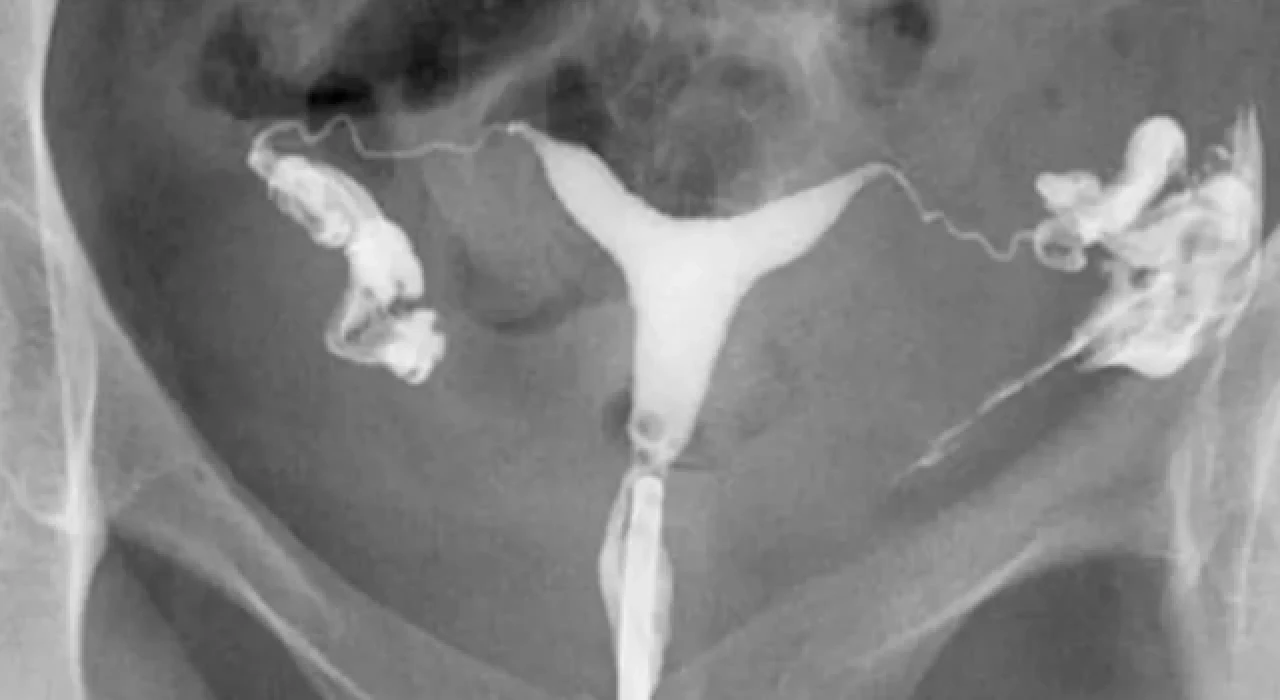

Rahim filmi, tıbbi ismiyle histerosalpingografi (HSG), rahim ve fallop tüplerinin radyolojik olarak görüntülendiği bir tetkiktir. Bu işlem sırasında rahime özel bir boyar madde enjekte edilir ve X-ışını yardımıyla bu bölgelerin görüntüsü alınır. Rahim filmi, kadınların üreme sağlığını değerlendirmek amacıyla özellikle kısırlık soruşturmalarında ve tüp yollarının açıklığını kontrol etmek için kullanılır.

Rahim filmi, kadınların üreme sağlığıyla ilgili sorunları değerlendirmek amacıyla çektirilir. Özellikle kısırlık sorunları, tüp tıkanıklığı ya da rahimdeki potansiyel şekil bozuklukları gibi durumların teşhisinde etkili bir yöntemdir. Aynı zamanda tekrar eden düşüklerin nedenini araştırmak veya pelvik ağrının kaynağını belirlemek için de doktorlar tarafından önerilebilir.